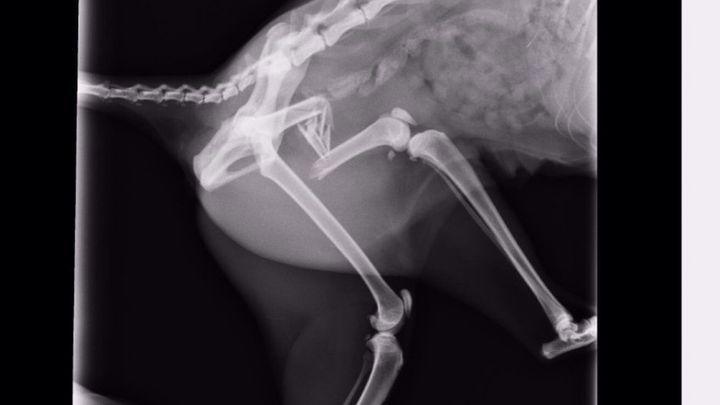

Kitty femur surgery.

“My cat has been hitten by a car yesterday. The x-ray radiography show us that her femur is completely destroyed. We don't know who has been, since he or she flew away in the accident. Now she needs to be sedated in total rest for 24 hours. The surgery costs 750 €, I'm completely shattered because we don't know how to pay it.”